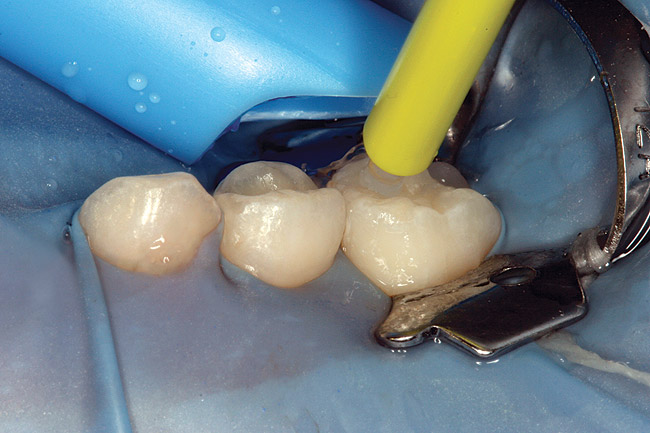

Specially designed dental wedges are inserted to slightly separate the carious tooth from adjacent teeth. A 15% hydrochloric gel is used to remove the "pseudointact" surface and open the pore system of the incipient lesion body (Figure 7).85 After rinsing (Figure 8), the area is dried with ethanol (Figure 9), followed by dry air. Then, the infiltrant is applied and allowed to penetrate the lesion pores by capillary action for 3 minutes (Figure 10). Any excess material is removed with dental floss, and the infiltrant is light cured from three angles for 40 seconds (Figure 11). A second layer of infiltrant is applied for 1 minute, and light cured for 40 seconds (Figure 12).86 It should be noted that the infiltrant is not radiopaque because fillers would affect the viscosity. Efficacy of the treatment can be tracked at future visits by lack of lesion progression.

Figure 10  Icon Infiltrant flowing through matrix channel into contact area on mesial of tooth A.

Figure 10

Figure 11  Light curing of infiltrant material.

Figure 11

Figure 12  Final view showing treated surface of mesial of tooth A.

Figure 12